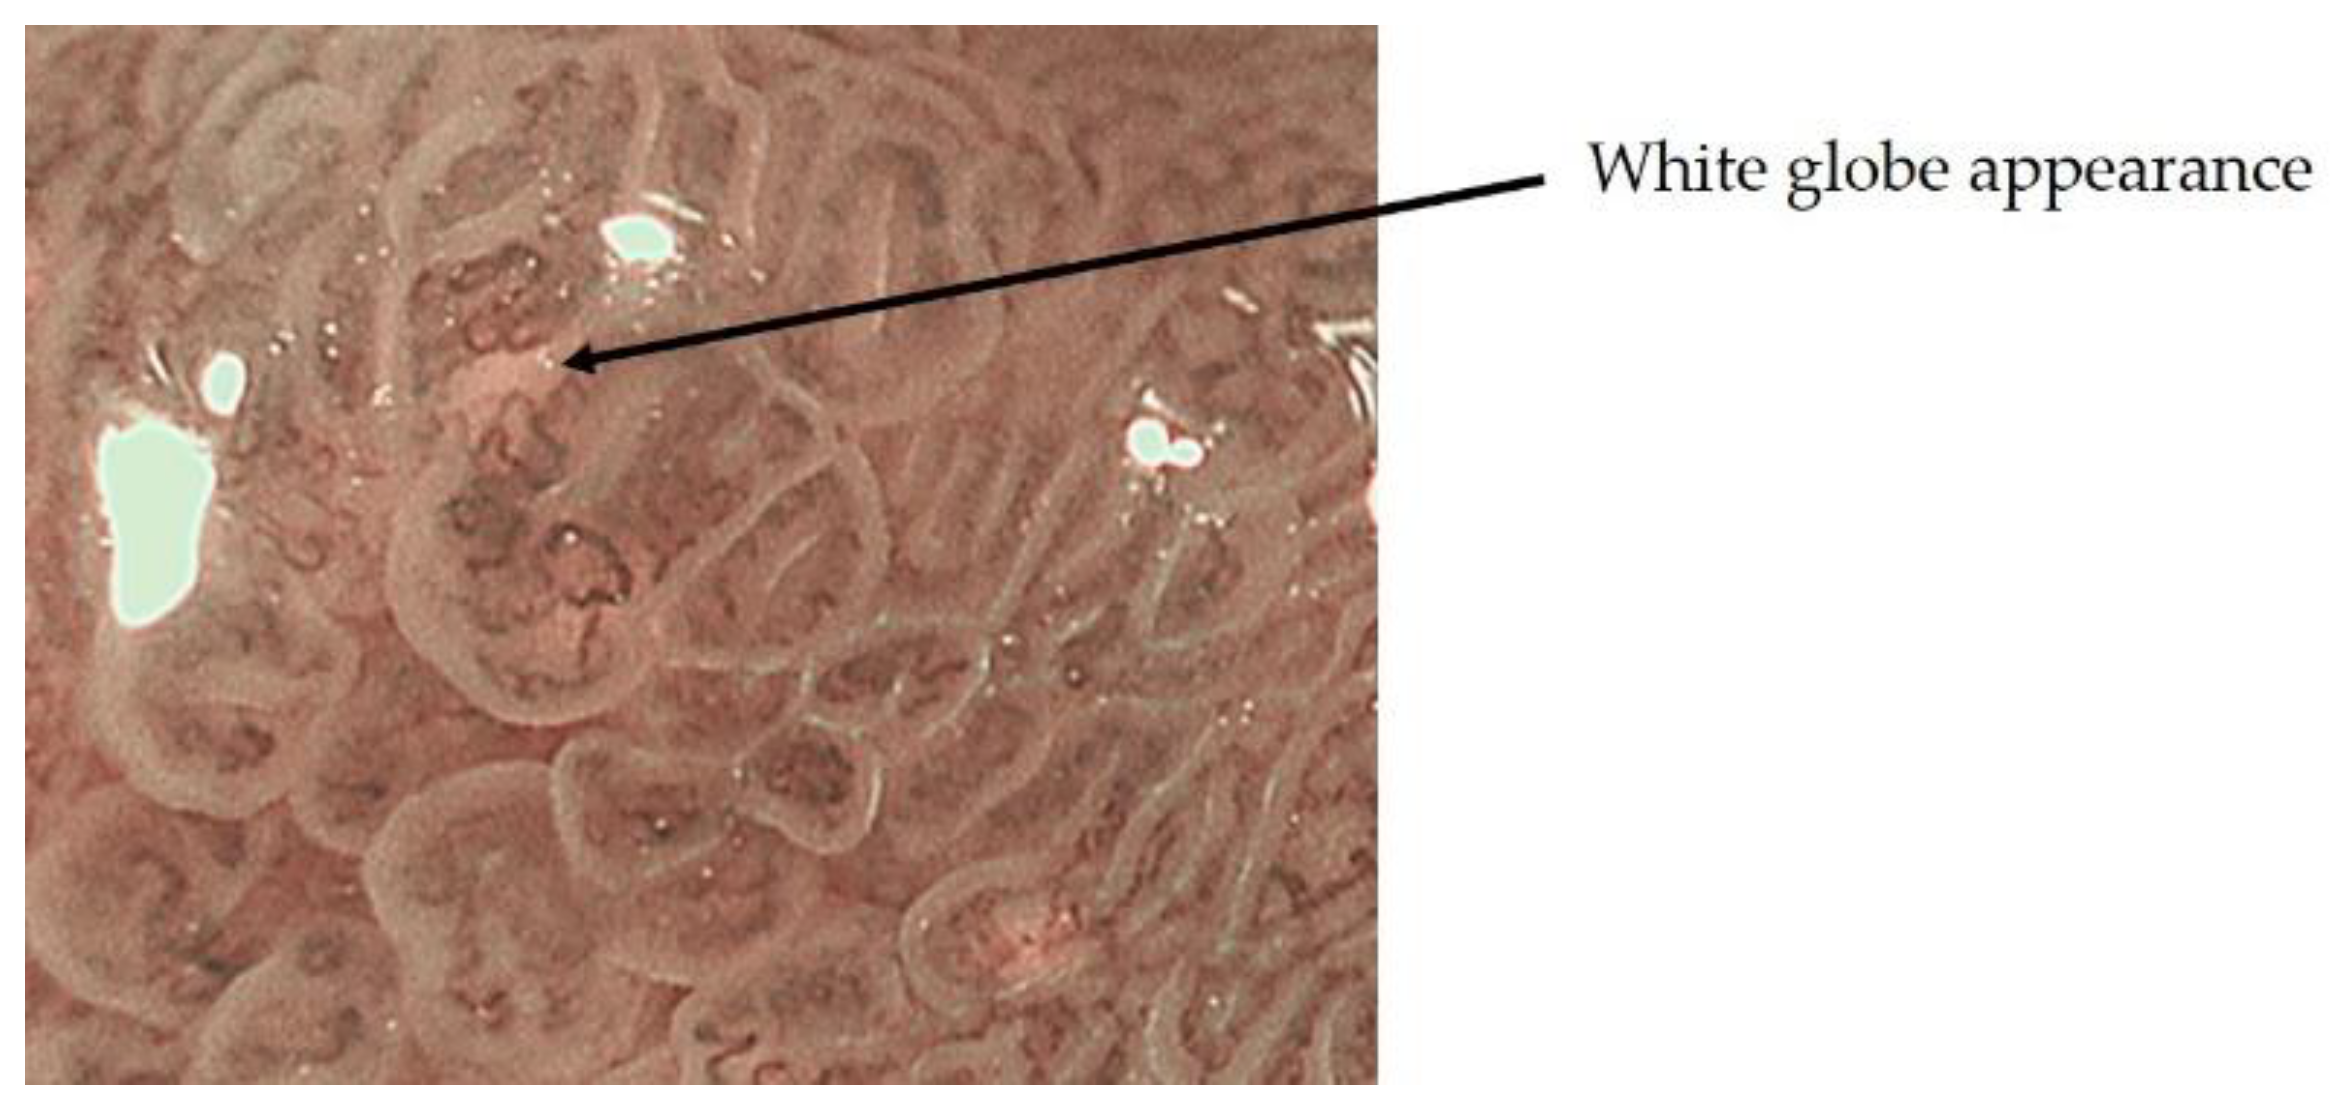

- Doyama, H.; Yoshida, N.; Tsuyama, S. The “white globe appearance”(WGA): A novel marker for a correct diagnosis of early gastric cancer by magnifying endoscopy with narrowband imaging(MNBI). Gastroenterol. Endosc. 2015, 57, 2577. [Google Scholar] [CrossRef] [Green Version]